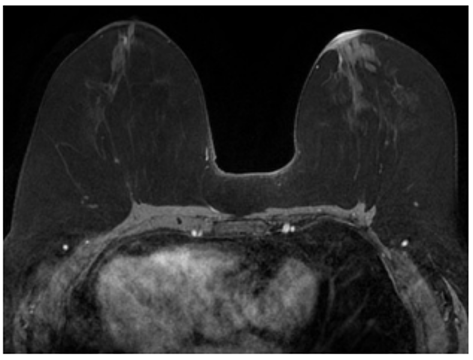

What clinical history most likely accounts for the imaging findings shown?

Bilateral reduction mammoplasty